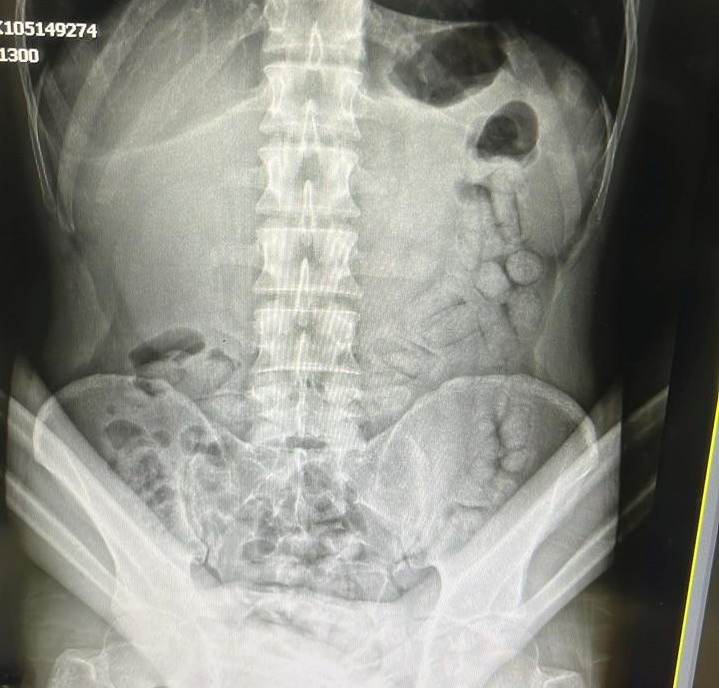

Gözaltına alınan şahsın adli makamların talimatıyla Gümüşhane Devlet Hastanesinde çekilen röntgeninin ardından yaptırılan iç beden muayenesinde 55 adet kapsül halinde 317,46 gram metamfetamin maddesi ele geçirildi.